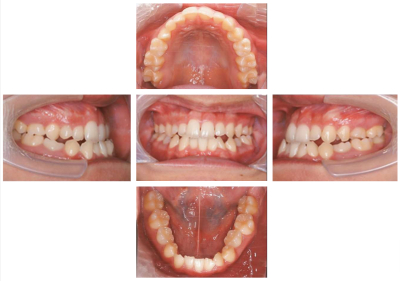

16 歳の女子。下顎の突出感と上顎右側乳犬歯の晩期残存を主訴として来院した。他に特記すべき既往はない。初診時の口腔内写真とエックス線画像を別に示す。先天欠如歯はどれか。1つ選べ。